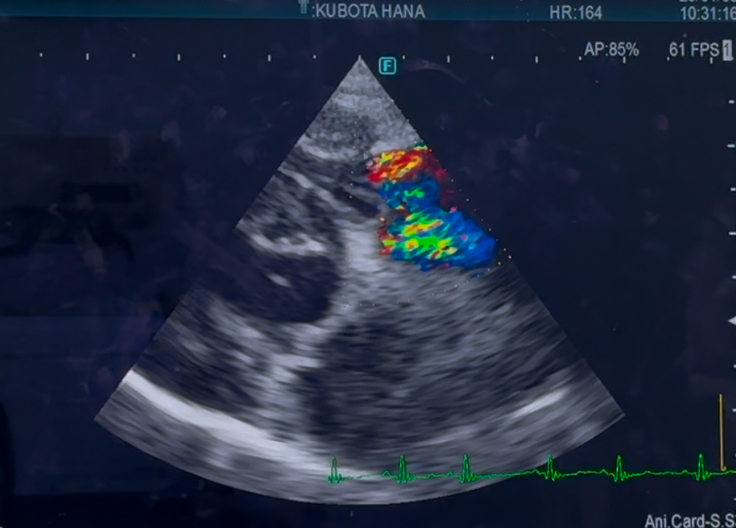

心臓手術後 1年4ヶ月検診でした

心臓手術後検診(1年4ヶ月)でした

手術した、左心の方は

変わらず逆流は、あるものの

悪化はみられず、変わりなしでした

右心の、三尖弁の逆流は

少し、増えているかも…とのことでしたが

多少の、増減はあるものだと言うことと

数値より、症状があるかどうかにより

対処療法を、していくので

今現在は、咳もほとんどなく

症状は、みられないので

経過見となりました…